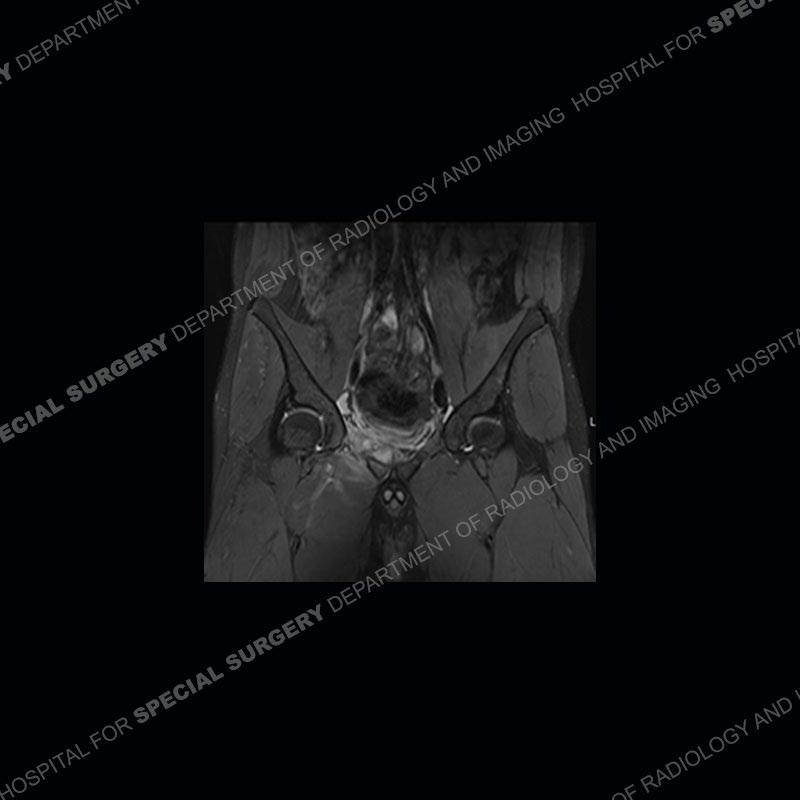

Radiographs did not demonstrate any clear abnormality. The MRI shows markedly abnormal signal of the right superior pubic ramus and abnormal signal/”mass” extending into the adjacent soft tissue. The inferior articular surface of the ramus showed what was thought to be bony destruction. CT examination shows a destructive process of the right superior pubic ramus.

Subsequent MRI in a very short time interval shows markedly increased abnormality of the ramus and increased edema and “mass” of the soft tissue. Post contrast imaging shows multiple, rim enhancing collections of the soft tissue and similar albeit less conspicuous enhancing collection of the ramus.